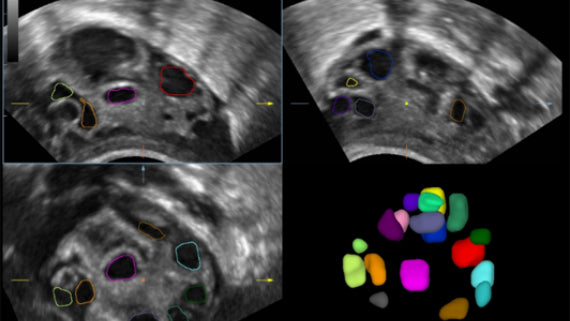

Como una solución de obstetricia, ginecología e imagen general completa, proporciona una interfaz muy robusta e intuitiva. Supera las expectativas de tus rastreos con su sistema de transductores pure crystal